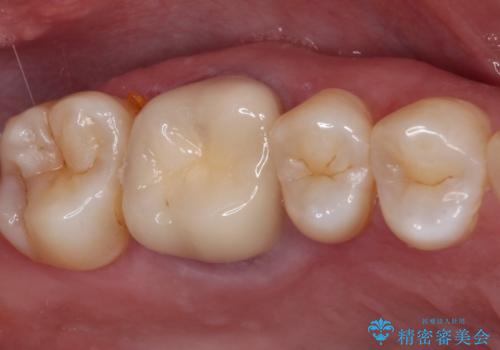

- 上下の奥歯に違和感を感じ、近医にて虫歯を指摘されたとのことで来院された患者様です。

診査したところ、下顎の奥歯は膿の出口ができており、上顎の奥歯は噛んだときに痛みを感じている状態でした。

まずは根管治療を行い、症状が落ち着いたことを確認して、オールセラミッククラウンにて補綴治療を行うこととしました。

処置後、下顎の膿の出口はすぐに消えましたが、レントゲン写真からも分かるとおり、歯根途中に穴が開いており、充填材が歯根外にはみ出していました。数ヶ月経過を見たところ、特に異常は認められなかったため、補綴治療を行いました。